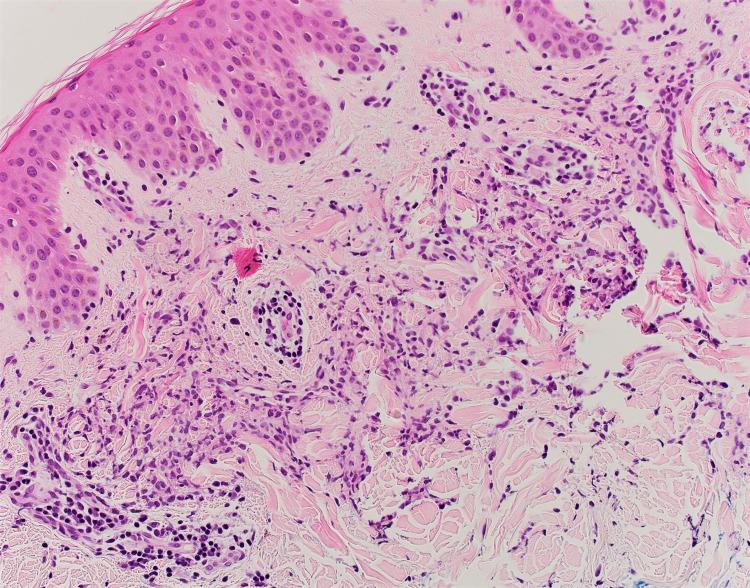

Interstitial granulomatous dermatitis (IGD) is a rare dermatological disorder. It is most commonly associated with autoimmune disorders mainly lupus and rheumatoid arthritis. It has rarely been reported to present as a first manifestation of an underlying vasculitis. Here, we present a case of a 44-year-old woman who presented initially with a violaceous rash starting in her neck and trunk and extending to her limbs, but sparing the palms and soles. She was also found to have an acute kidney injury. A biopsy of the skin lesion confirmed the diagnosis of IGD, and a kidney biopsy showed findings consistent with granulomatosis with polyangiitis. To the best of our knowledge, this is the seventh reported case of IGD associated with systemic vasculitis.

间质性肉芽肿性皮炎(IGD)是一种罕见的皮肤病。它最常与自身免疫性疾病相关,主要是狼疮和类风湿性关节炎。很少有报道称它是潜在血管炎的首发表现。在此,我们报告一例44岁女性病例,该患者最初表现为颈部和躯干出现紫红色皮疹,并蔓延至四肢,但手掌和脚底未受累。她还被发现患有急性肾损伤。皮肤病变活检确诊为IGD,肾脏活检结果与肉芽肿性多血管炎一致。据我们所知,这是第七例报道的与系统性血管炎相关的IGD病例。